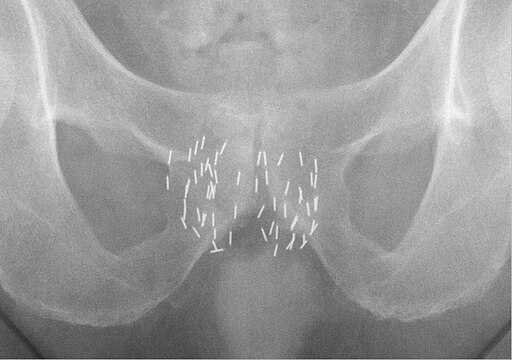

Paired ovals, the testes are each approximately 4 to 5 cm in length and are housed within the scrotum (see Figure \(\PageIndex{2}\)). They are surrounded by two distinct layers of protective connective tissue. Immediately deep to the cremaster muscle is the tunica vaginalis. The outer tunica vaginalis is a serous membrane that has both a parietal and a thin visceral layer. Beneath the tunica vaginalis is the tunica albuginea, a tough, white, dense connective tissue layer covering the testis itself. Not only does the tunica albuginea cover the outside of the testis, it also invaginates to form septa that divide the testis into 300 to 400 structures called lobules. Within the lobules, sperm develop in structures called seminiferous tubules (Figure \(\PageIndex{3}\). During the seventh month of the developmental period of a male fetus, each testis moves through the abdominal musculature to descend into the scrotal cavity. This is called the “descent of the testis.” Cryptorchidism is the clinical term used when one or both of the testes fail to descend into the scrotum prior to birth.